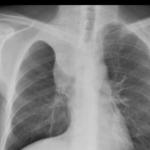

Signs

Album: Signs

Date: 04/28/2014

Size: 29 items

Views: 66909